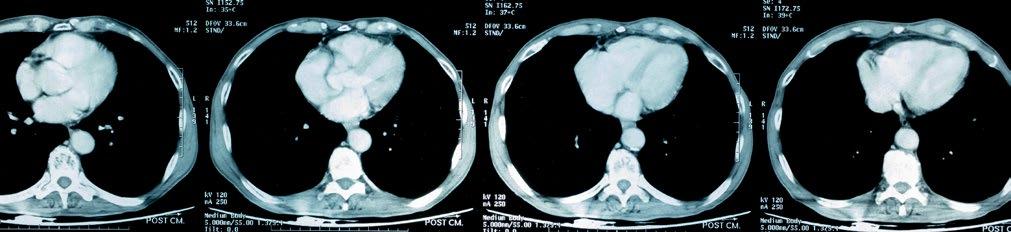

Exophytic lesion shows a central dimple or spicule at the apex of mass, as a result of traction in the gastric or bowel wall by the base of mass, thus helping to differentiate it from the extrinsic lesion.3 Findings on CT (the primary modality of choice for GIST): small GIST (<5 cm) show homogeneous enhancement and are round in morphology, while large GIST (>5 cm) are lobulated with heterogeneous enhancement, and are associated with degenerative changes, like necrosis, haemorrhage, and very rarely, calcification and metastasis as well.2,6,19,20

Irrespective of the tumour size, there is mucosal ulceration which leads to GI bleeding. Cavitation is also seen in GIST, which leads to air entrapment in the necrotic ulcer (Torricelli–Bernoulli sign). Necrosis and ulceration are common as it outgrows the blood supply, or if the endophytic growth causes thinning and stretching of the overlying mucosa layer.3

Gastric GIST shows an intermediate pattern of enhancement, while small bowel GIST shows marked arterial phase enhancement. ‘Tumour vessel’ sign, a feature of small bowel GIST due to early venous return and prominence of the draining vein, helps in tracing the origin of the tumour. A nodule within the mass is a sign of recurrence.1 Treatment of choice for resectable GIST is surgery, although neoadjuvant imatinib is given to reduce the tumour size, and postsurgery imatinib is administered to prevent recurrence of the disease for at least 3 years. In case of metastasis or recurrence, imatinib is a first line drug.4,10,11,20

CONCLUSION

Although CT is the modality of choice for GIST, it is imperative for a radiologist to be wellacquainted with various other non-cross section imaging, such as radiographs, small bowel series, and ultrasound, to increase the level of confidence in radiological diagnosis before histopathology and immunohistochemistry confirms it.

Creative Commons Attribution-Non Commercial 4.0 ● April 2024 ● Radiology 91 Case Report

References

1. Inoue A et al. Gastrointestinal stromal tumors: a comprehensive radiological review. Jpn J Radiol. 2022;40(11):1105-20.

2. Levy AD et al. Gastrointestinal stromal tumors: radiologic features with pathologic correlation. Radiographics. 2003;23(2):283304.

3. Gore RM et al. "Benign tumors," Levine MS, Gore RM (eds.), Textbook of Gastrointestinal Radiology Volume One (1994), Philadelphia: Saunders, pp.4358;640-4.

4. Udina EL, Fisher KL. Sonographic detection of a gastrointestinal stromal tumor of the stomach. J Diagn Med Sonogr. 2016;32(4):211-6.